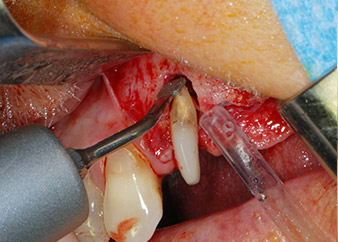

Puis l'apex a été limé à l'aide du même instrument afin d'éliminer les tissus apicaux infectés résiduels et de réduire les éventuelles ramifications des canaux radiculaires (apicectomie) (Fig. 5). Il n'a pas été nécessaire de procéder à une obturation rétrograde car l'obturation orthograde venait juste d'être reprise.

apicectomie de la dent 24

Fig 5 : ...et l'apex de la dent 24 a été limé avec le même instrument (apicectomie).